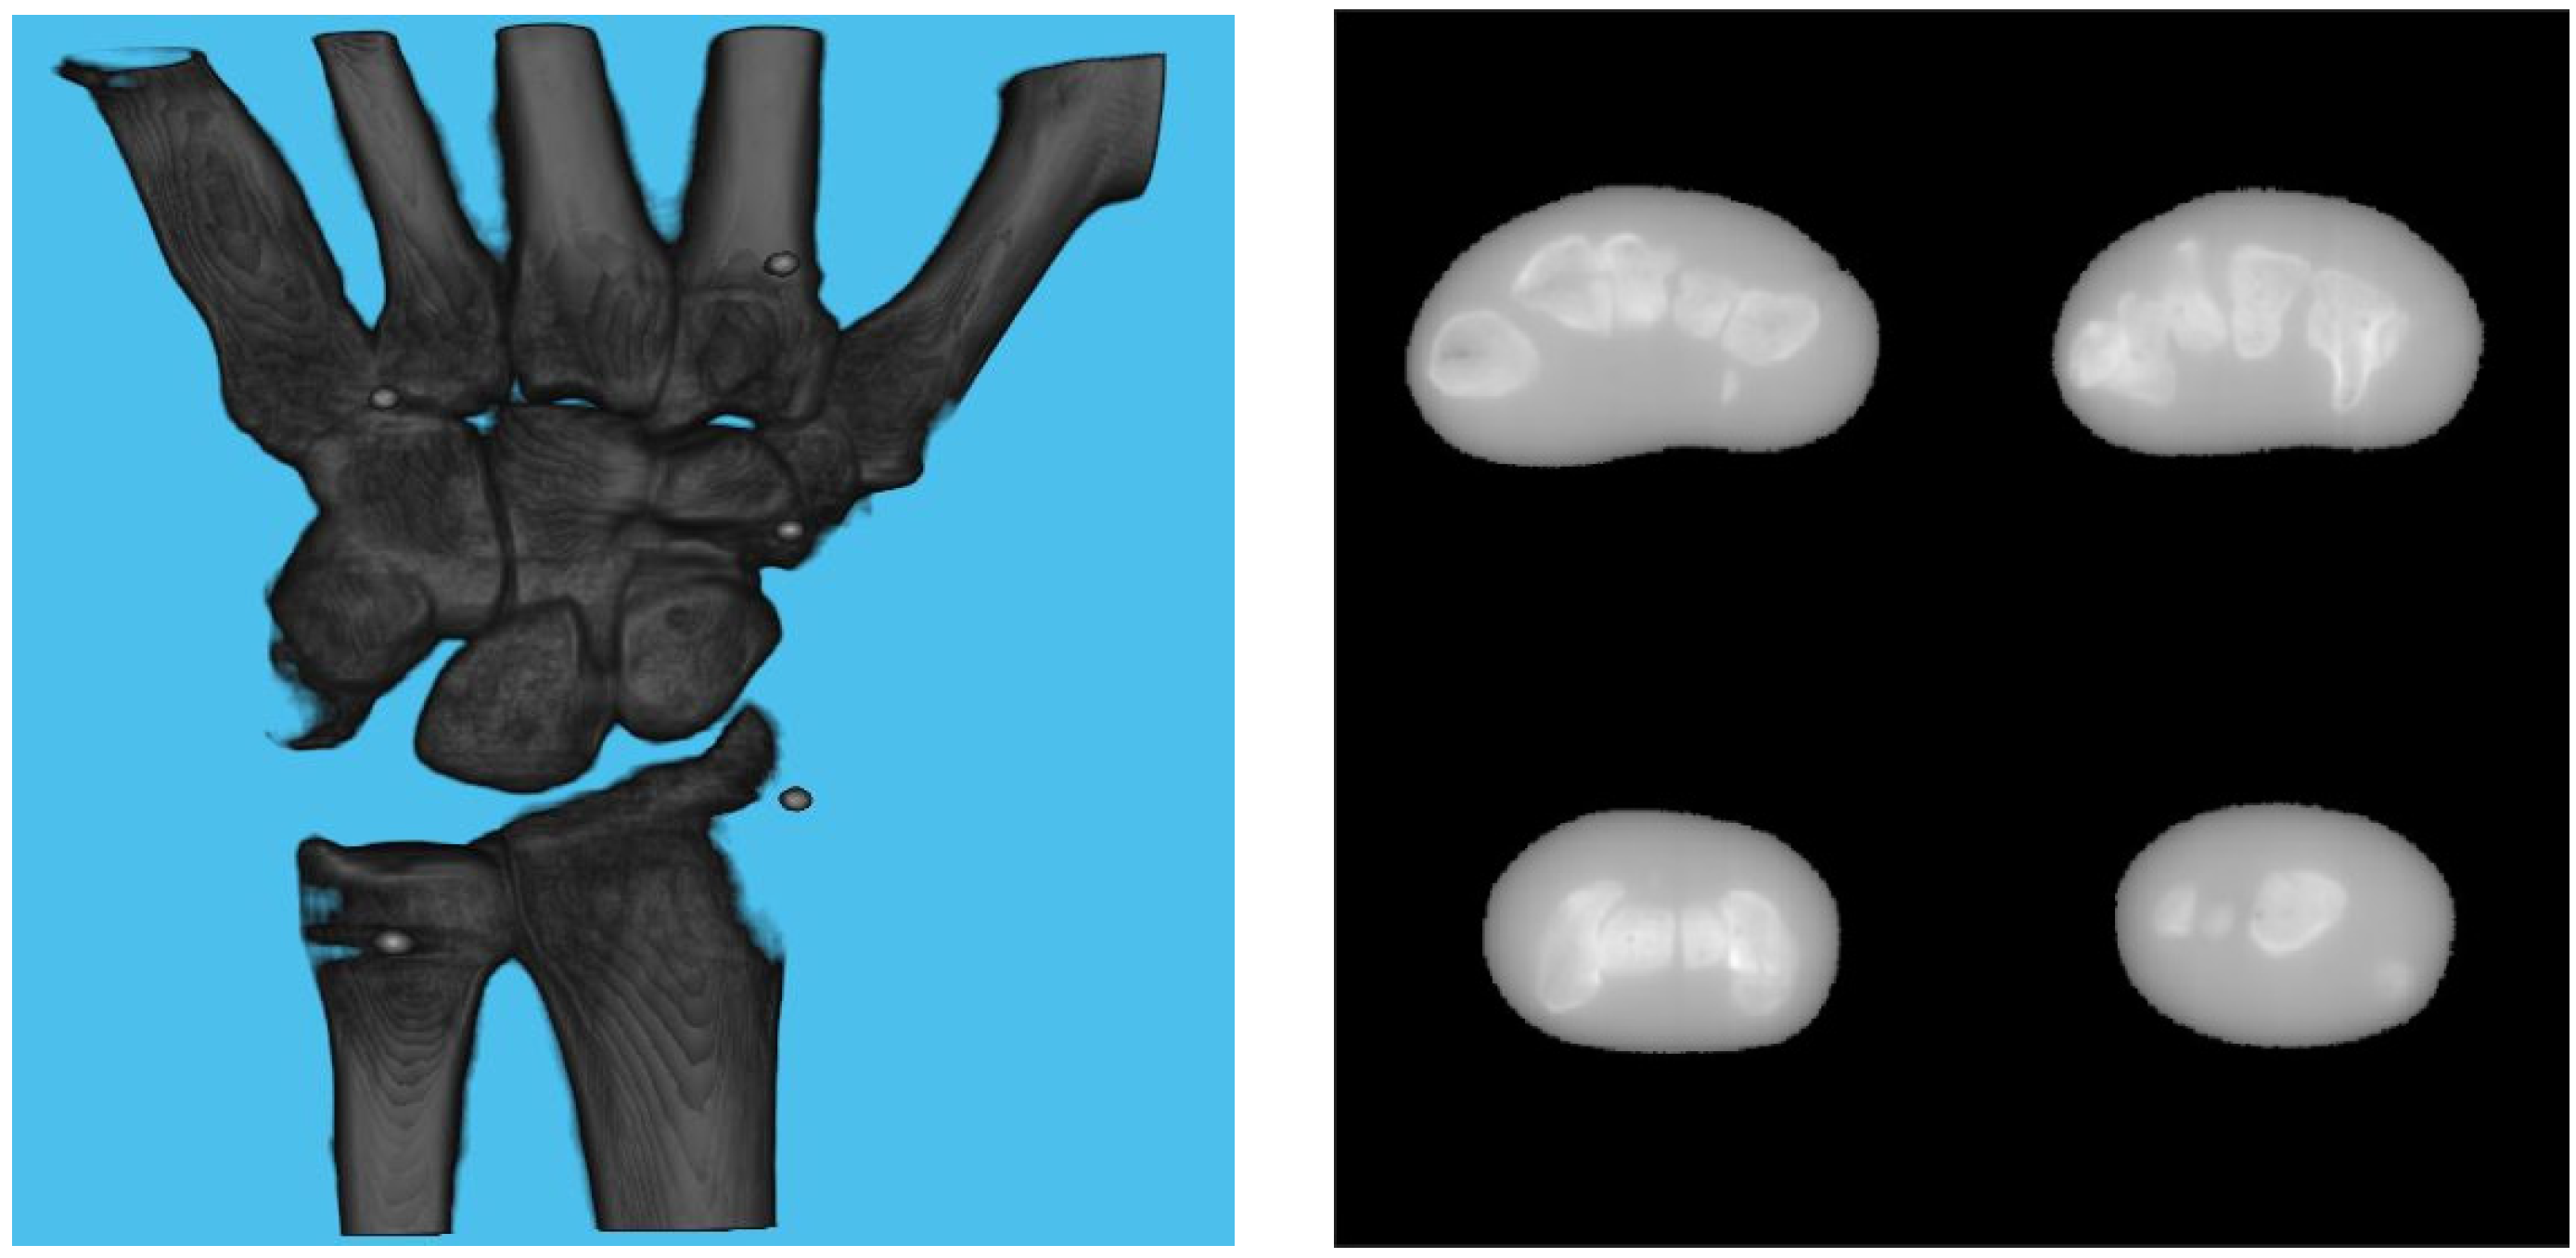

3. Experiments and Results

3.1. Simulation Setup

3.2. Effect of Board Thicknesses and Marker Sizes on Reconstructed Image Quality